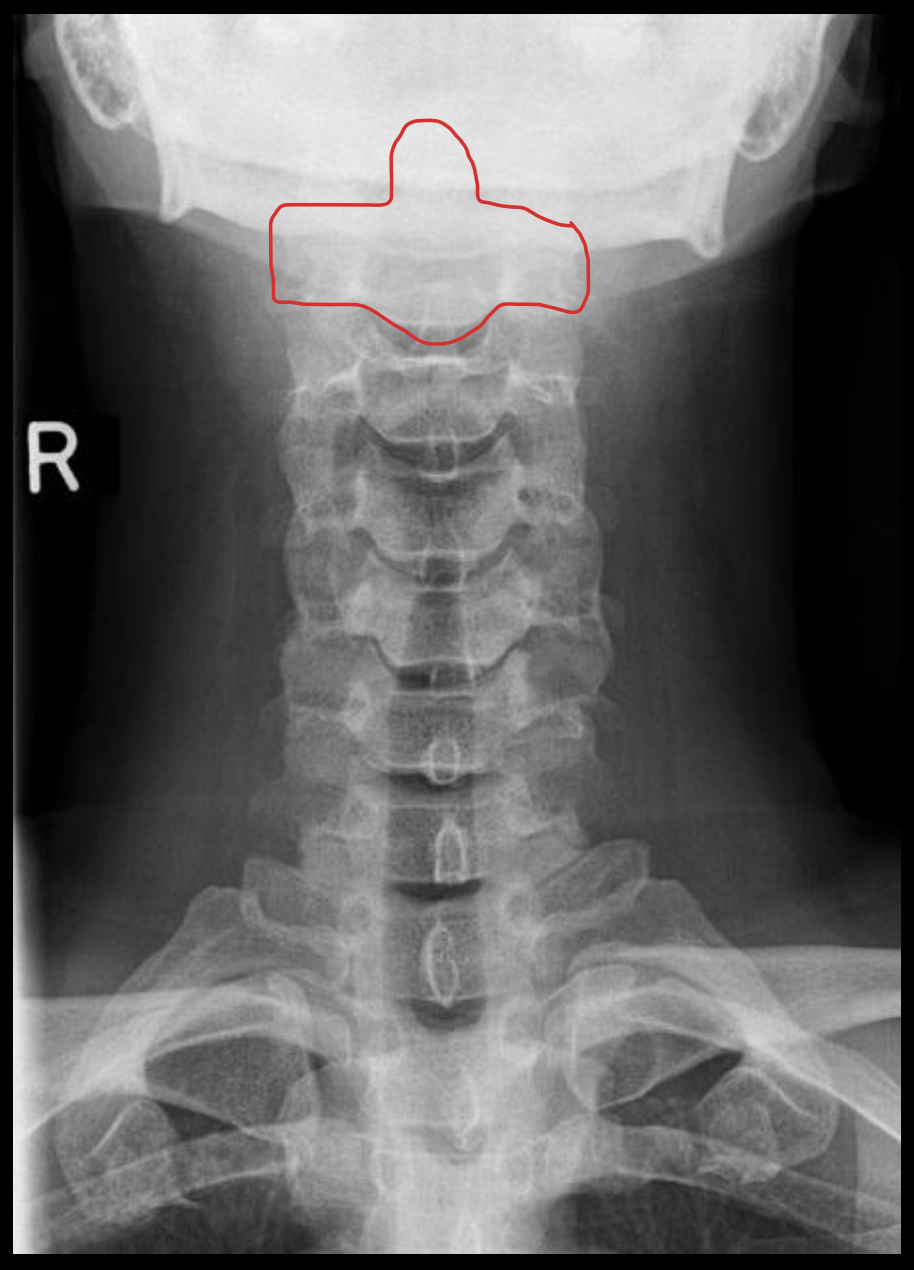

齿状突

Odontoid process C1

C2

寰枢关节

Atlanto-axial

寰椎侧块

C1 lateral mass

枢椎棘突

C2 spinous process

寰椎后弓

Posterior arch C1

寰椎横突

C1 transverse process

C1